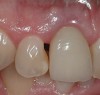

Figure 4  Characterization of the interproximal bone and tooth contacts: A periapical radiograph assists in measuring the distance from bone crest to the adjacent tooth contact points for missing tooth No. 8. The mesial bone crest to the adjacent tooth contact distance is < 5 mm, while the distal bone crest to adjacent tooth contact distance is > 6 mm (Fig 4). One-year following implant placement, conservation of these dimensions is revealed (Fig 5). The clinical photograph (Fig 6) of the lateral incisor adjacent to tooth No. 8 implant crown demonstrates that the absence of distal interproximal (papilla) fill related to the observed bone crest to contact distance exceeds 6 mm.

Figure 6  Characterization of the interproximal bone and tooth contacts: A periapical radiograph assists in measuring the distance from bone crest to the adjacent tooth contact points for missing tooth No. 8. The mesial bone crest to the adjacent tooth contact distance is < 5 mm, while the distal bone crest to adjacent tooth contact distance is > 6 mm (Fig 4). One-year following implant placement, conservation of these dimensions is revealed (Fig 5). The clinical photograph (Fig 6) of the lateral incisor adjacent to tooth No. 8 implant crown demonstrates that the absence of distal interproximal (papilla) fill related to the observed bone crest to contact distance exceeds 6 mm.

Figure 6